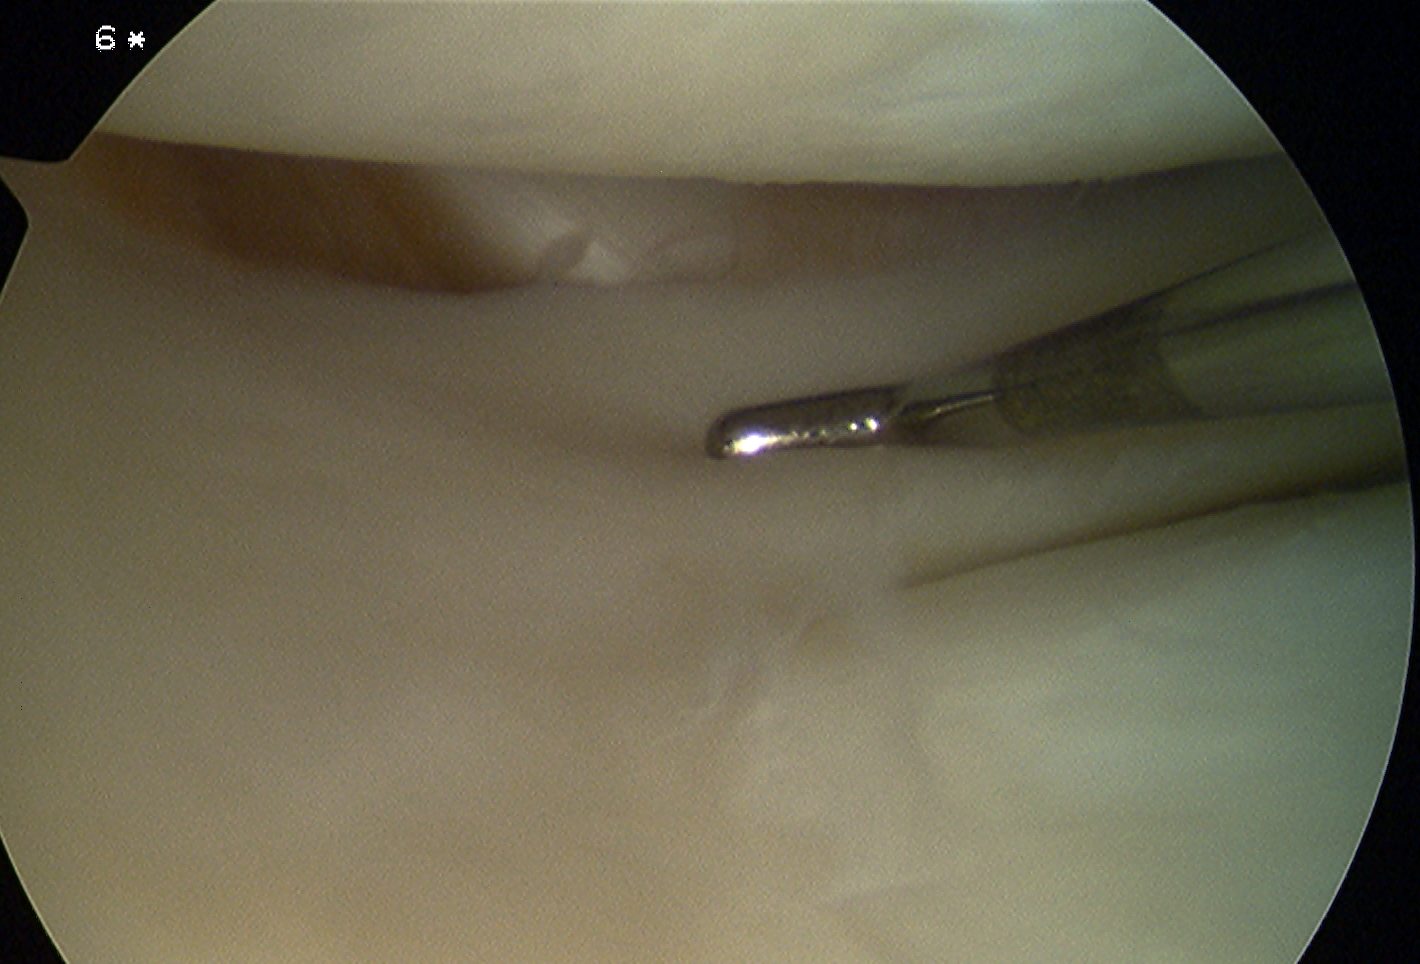

2. Popliteus tendon

Insertion

- tendon passes through capsule and hiatus in coronary ligament of lateral meniscus

- runs around lateral femoral condyle

- passes deep to LCL

- inserts into most anterior aspect of the popliteus sulcus

- always anterior and distal to LCL

- average 18.5 mm between LCL and popliteus femoral insertion

Arthroscopy of right knee showing intra-articular popliteus tendon behind lateral meniscus